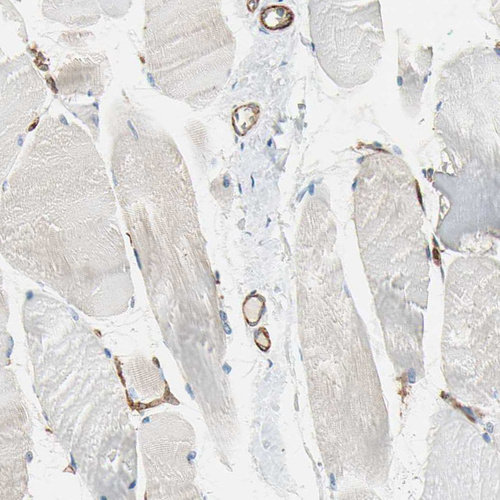

Immunohistochemistry analysis in human lung and skeletal muscle tissues using HPA009300 antibody. Corresponding CD93 RNA-seq data are presented for the same tissues.